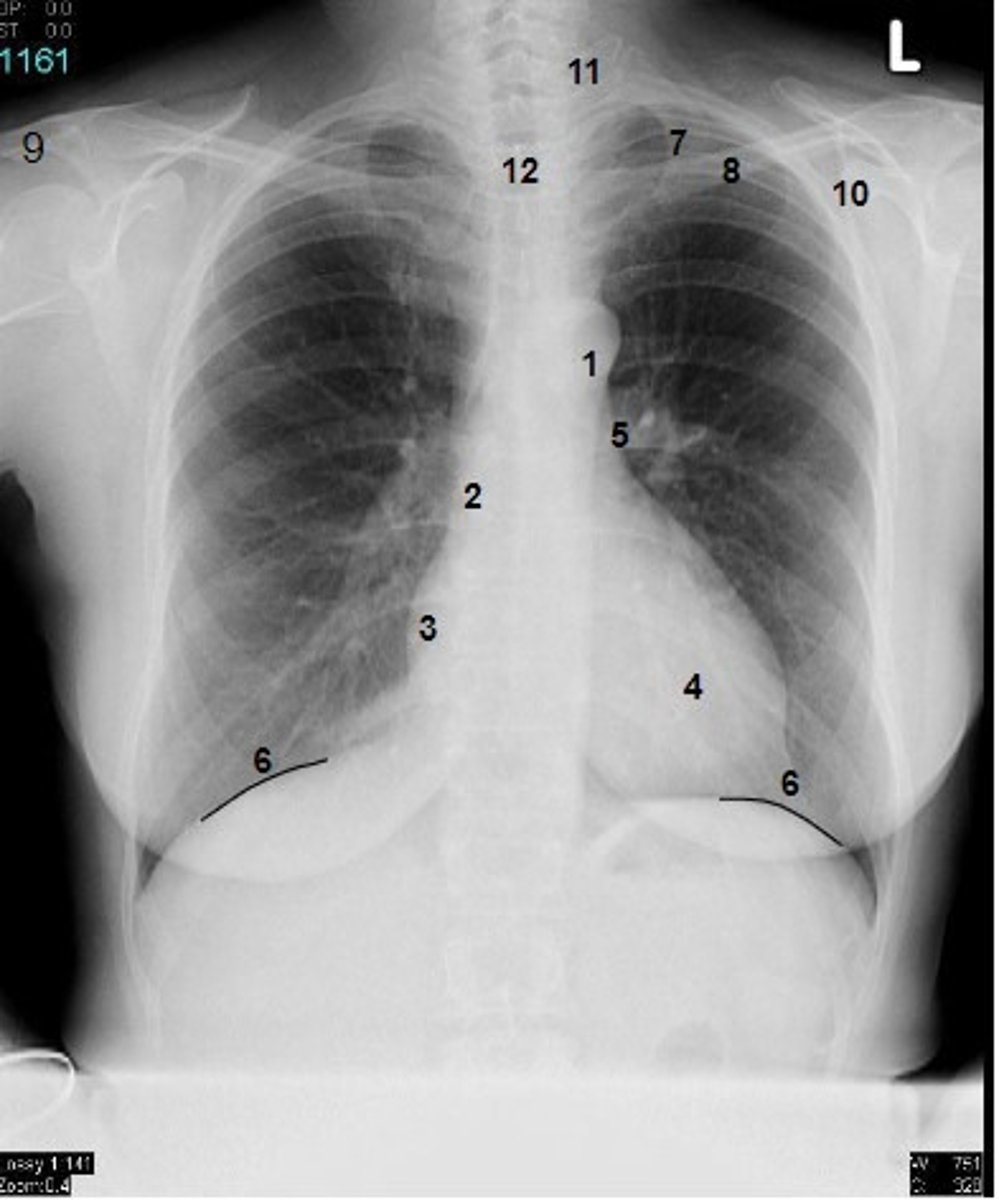

1

at what number is the arch of aorta?

2

at what number is the superior vena cava

3

at what number is the right atrium

4

at what number is the left ventricle

5

at what number is the primary bronchus

6

at what number is the dome of diaphragm

7

at what number is the first rib

8

at what number is the clavicle

9

at what number is the acromion of scapula

10

at what number is the coracoid process of scapula

11

at what number is the transverse process of vertebra

12

at what number is the spinous process of vertebra